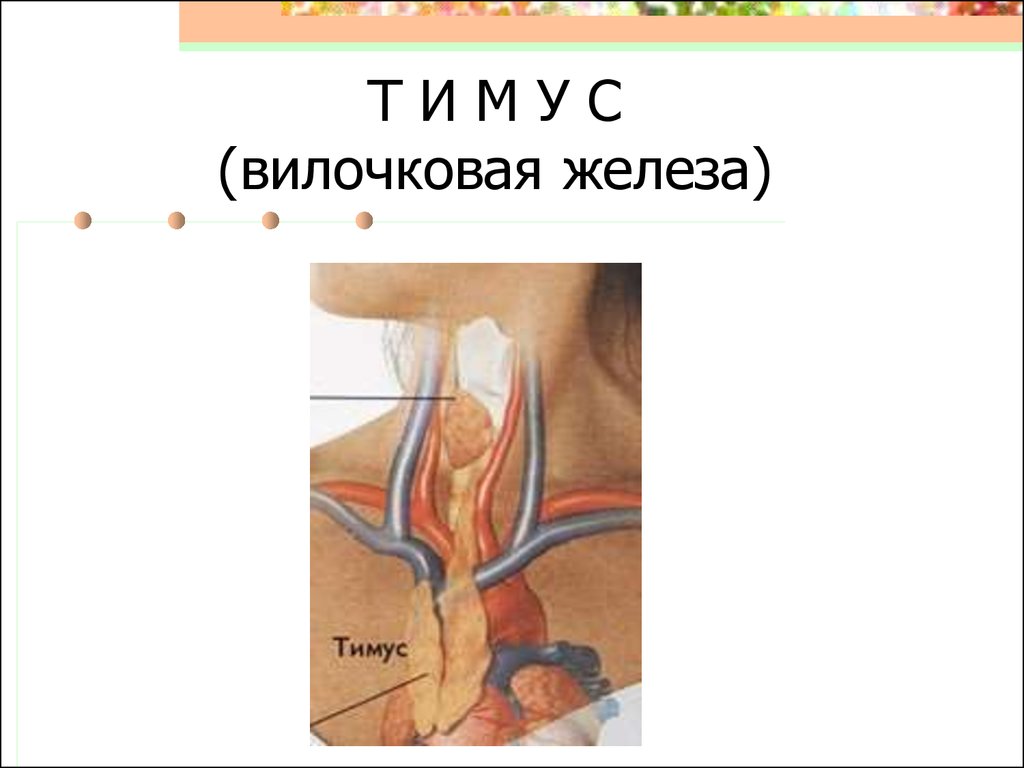

Фотографии вилочковой железы тимуса: структура и функции

Раздел: Снимки-откровения